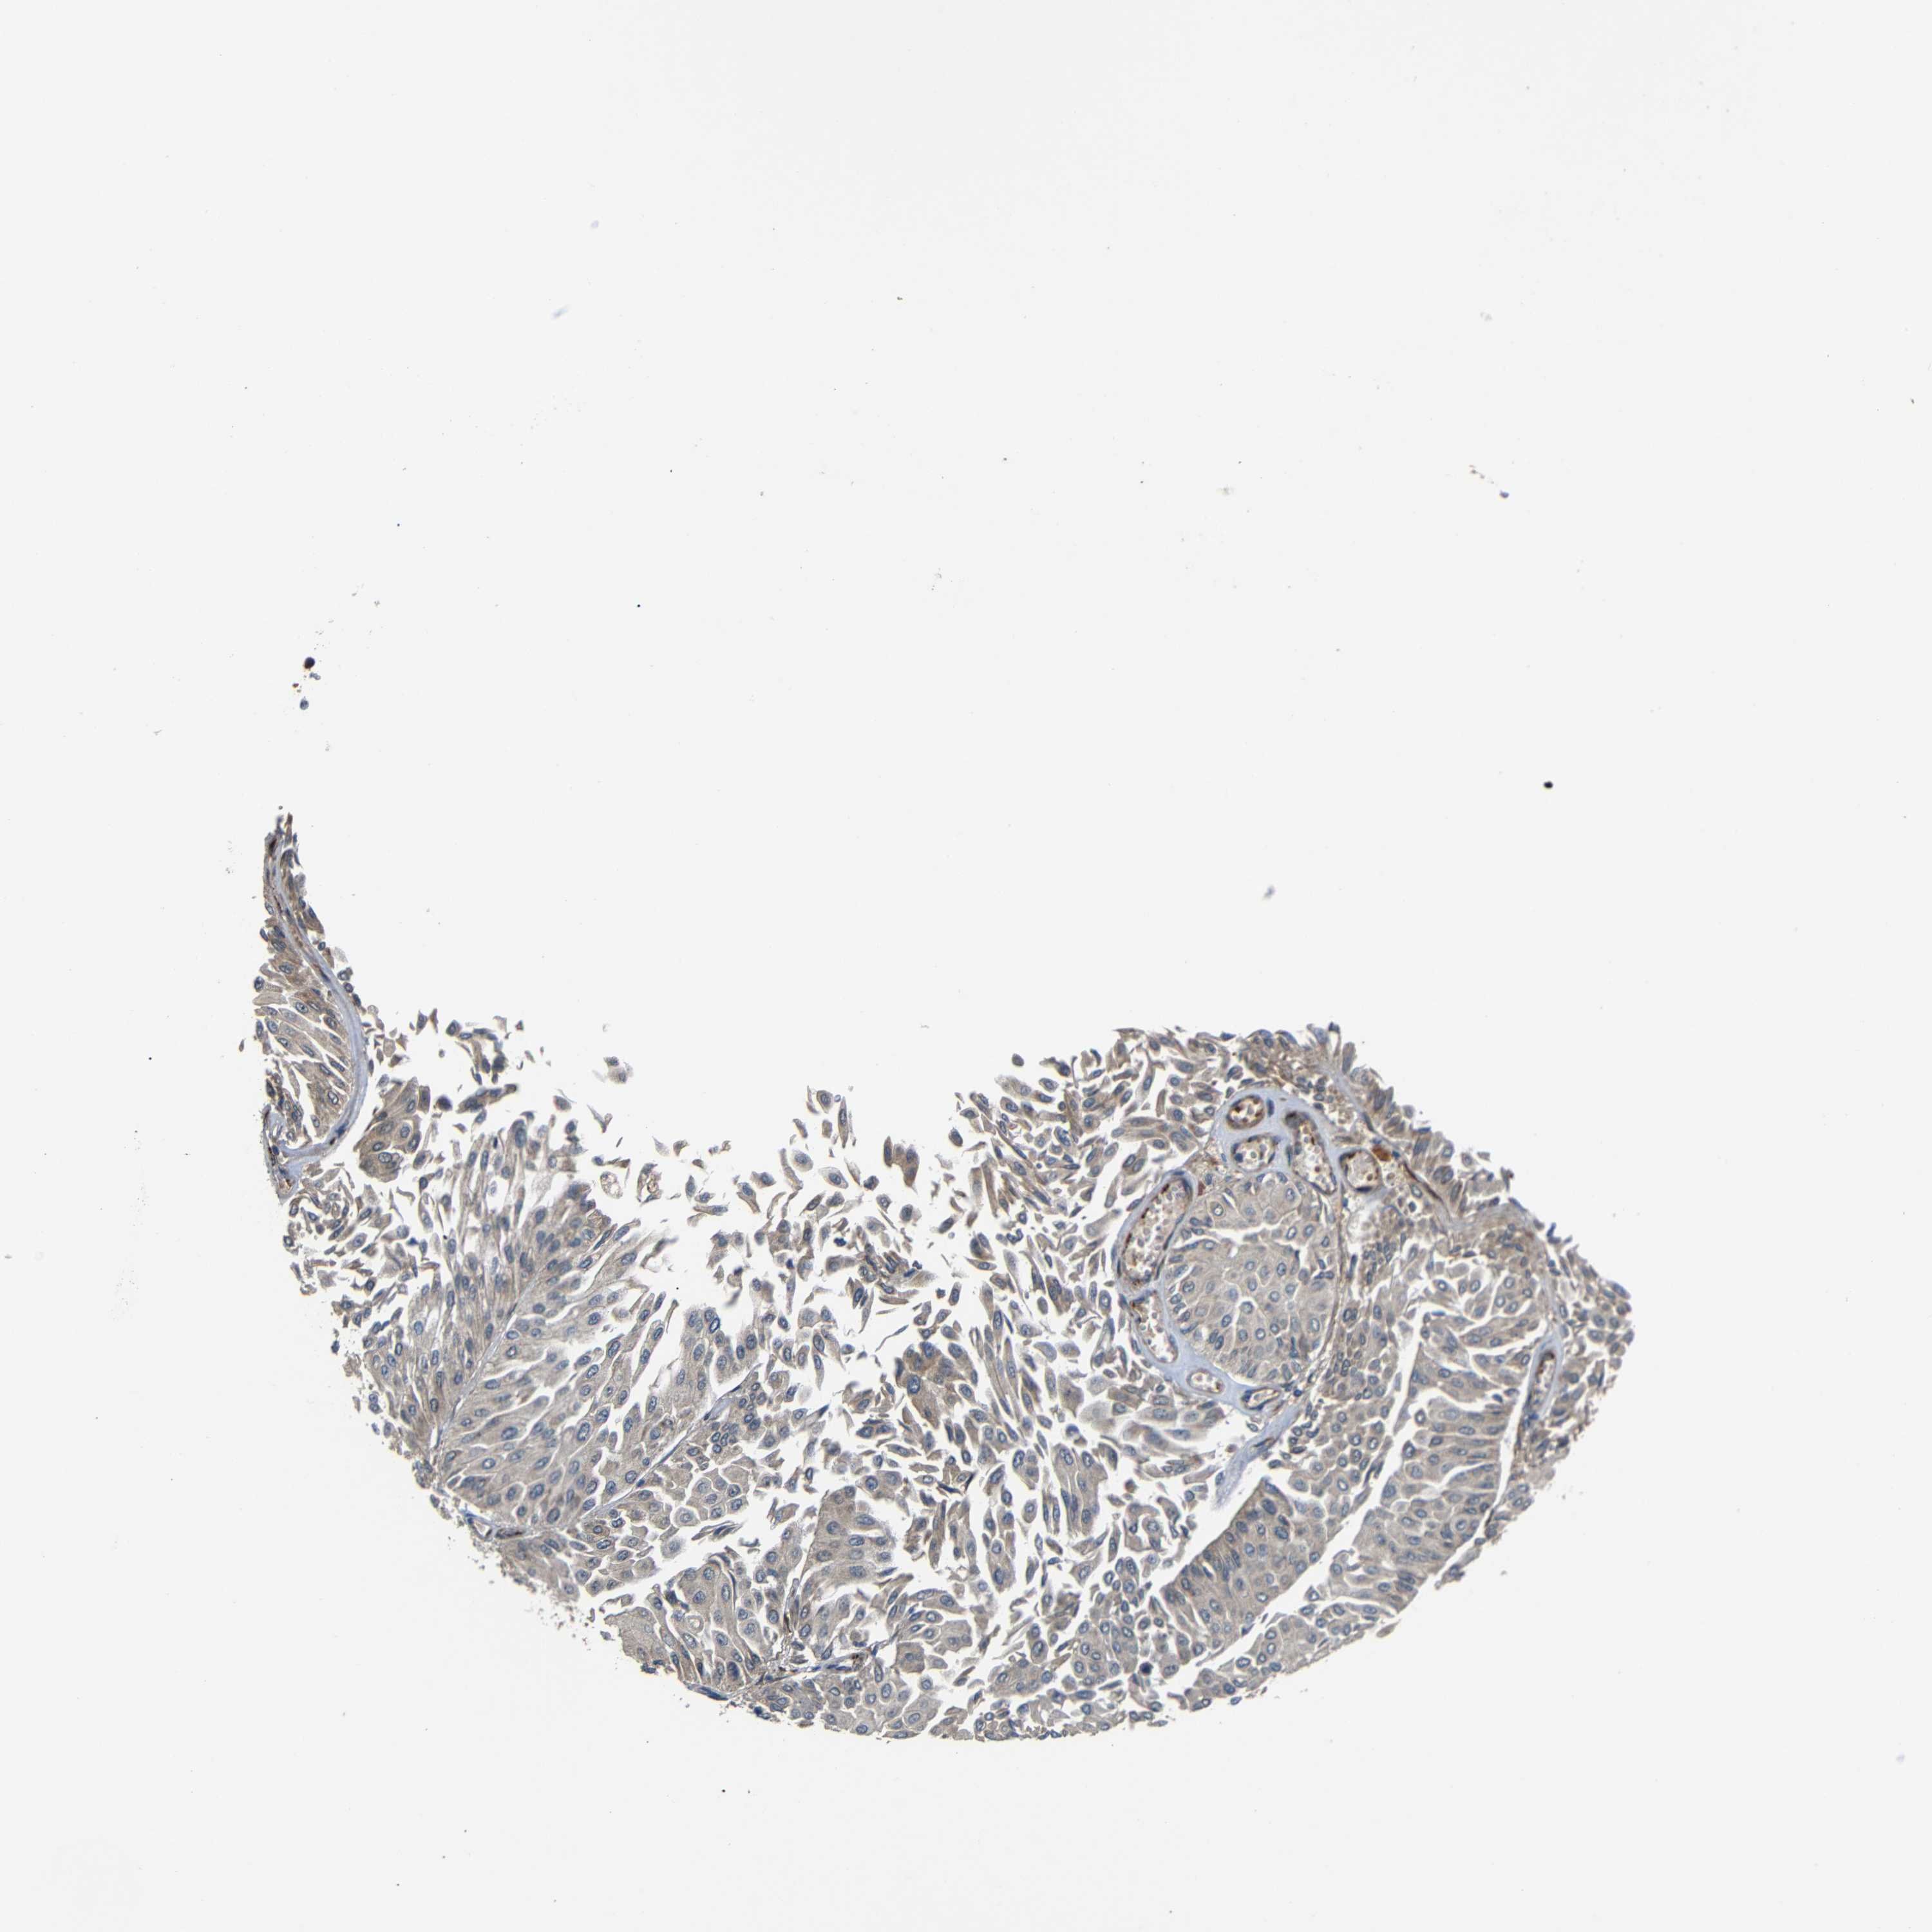

UROTHELIAL CANCER - Protein expressioni

A mouse-over function shows sample information and annotation data. Click on an image to view it in a full screen mode. Samples can be filtered based on level of antibody staining by selecting one or several of the following categories: high, medium, low and not detected. The assay and annotation is described here.

Note that samples used for immunohistochemistry by the Human Protein Atlas do not correspond to samples in the TCGA dataset.

Antibody stainingi

Antibody staining in the annotated cell types in the current human tissue is reported as not detected, low, medium, or high, based on conventional immunohistochemistry profiling in selected tissues. This score is based on the combination of the staining intensity and fraction of stained cells.

Each image is clickable and will lead to virtual microscopy that enables deeper exploration of all samples and also displays staining intensity scores, fraction scores and subcellular localization as well as patient and tissue information for each sample.

Antibody HPA012887

Staining

High

Medium

Low

Not detected

Intensity

Strong

Moderate

Weak

Negative

Quantity

>75%

75%-25%

<25%

None

Location

Nuclear

Cytoplasmic/membranous

Cytoplasmic/membranous,nuclear

Urothelial carcinoma, Low grade

Urothelial carcinoma, High grade